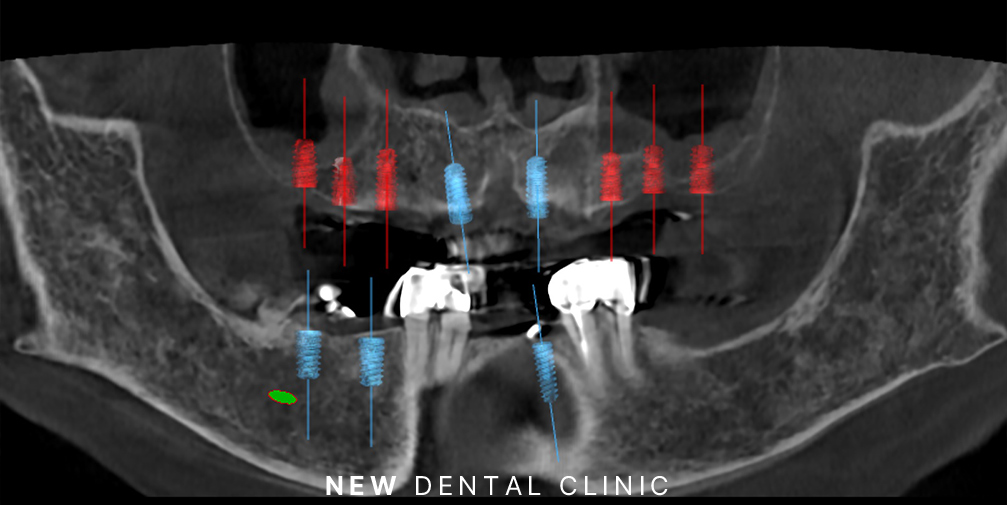

네비게이션 임플란트는 이러한 고민을 해결할 수 있는 방법으로 기존 수술법에서 더 발전된 기술로 CT를 활용하여 구강 내 해부학적 구조를 정밀하게 파악한 후, 그에 맞춰 식립하는 방법입니다. 3D CT를 통해 치아 상실 부위, 주변 치아, 신경, 치조골 상태 등을 정확하게 분석하고 이를 바탕으로 가이드를 제작하여 식립 과정에 따른 정확도를 높여 마치 자동차 네비게이션처럼 정확한 위치에 식립이 가능한 것입니다.

환자분께서는 겁도 많으셔서 수술에 대한 두려움이 있으셨는데요. 따라서 가이드를 이용한 네비게이션 임플란트로 계획을 수립하였습니다.

3D CT 촬영을 총해 가이드를 제작하여 장착한 모습인데요. 여러 개의 임플란트를 동시에 식립해야 하는 경우에도 계획을 통해 한 번에 진행할 수 있어 전체적인 치료 기간을 단축할 수 있다는 장점도 가지고 있습니다.